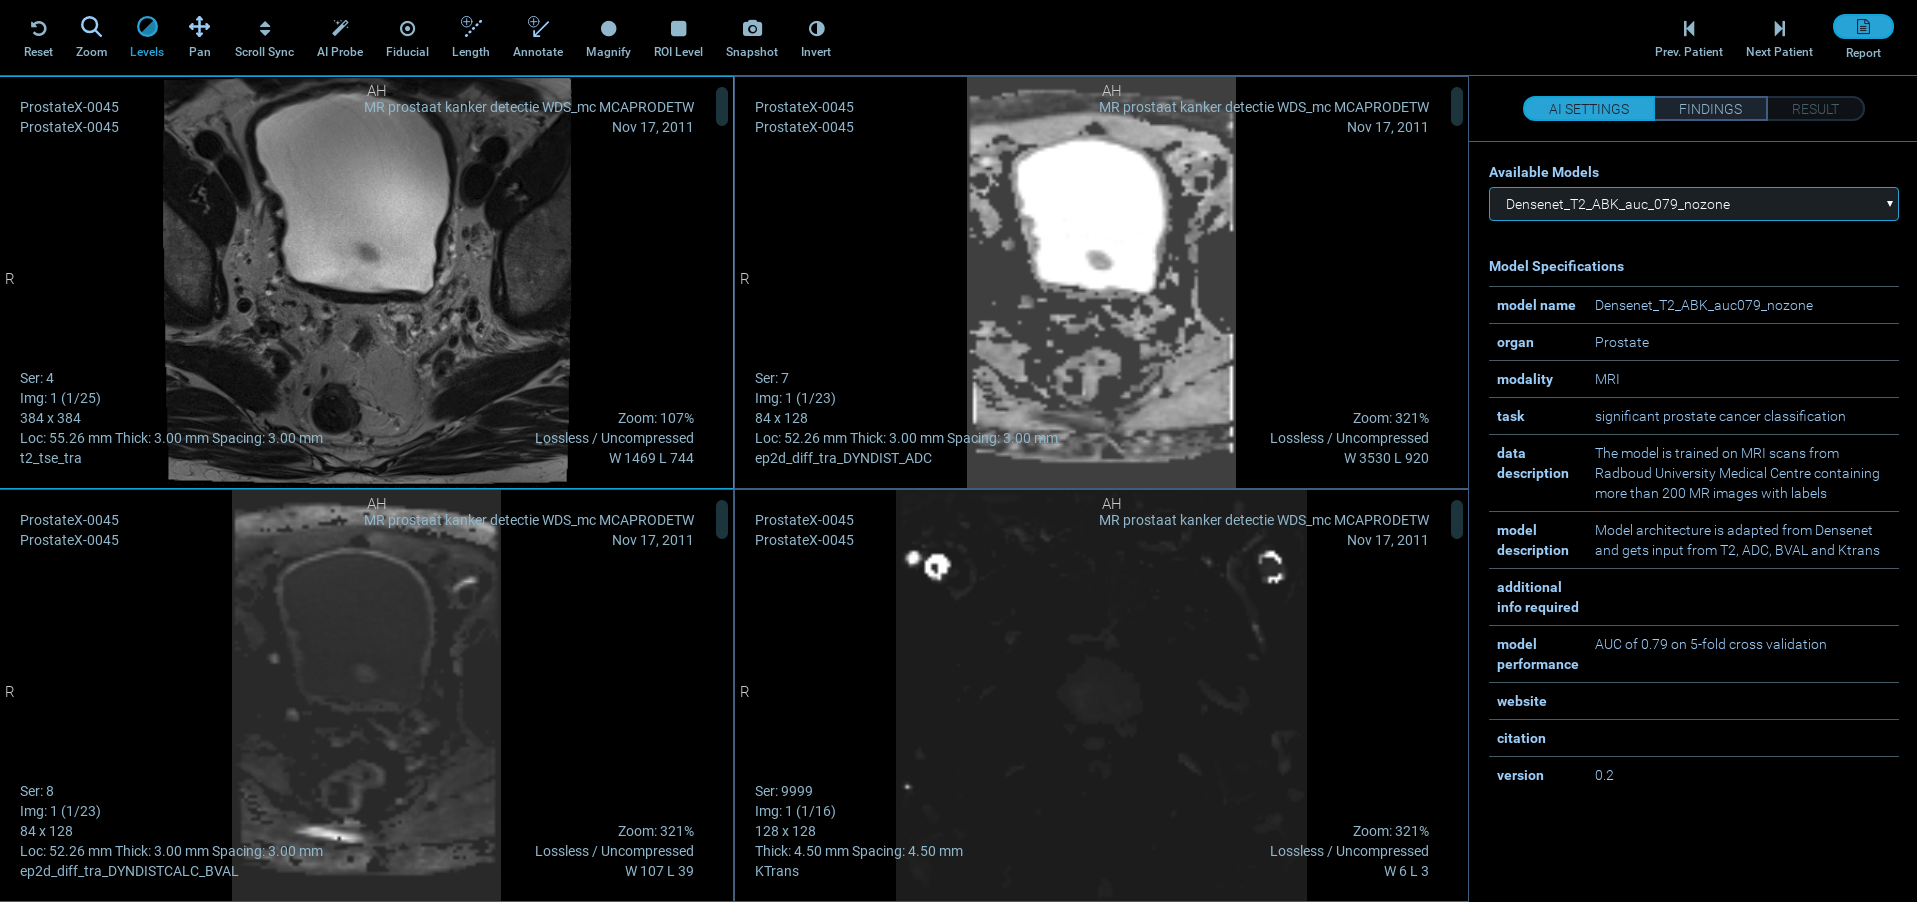

Flexible AI means you can choose the data set that best fits your use case, and apply it to your relevant medical images. We include a training set for Prostate Cancer as a starting point, but that’s only the beginning! The AI setting allows the user to choose the desired model from the list of all available models along with their descriptions.

For each case, the application presents 4 separate MR image stacks of T2-weighted images, ADC map, high b-value DWI, and Ktrans map obtained from contrast-enhanced imaging. After choosing the desired AI model, the user can locate the probe at any location on images to view the result of the AI prediction (the user can confirm or dismiss a finding after inspecting the AI prediction). The information will then be passed along to reporting using PI-RADS v2. The application gives the user a feedback message projection of the results on the 4 image views and histologically proven outcomes. Relative distances (in mm) between user-defined findings and biopsy locations are also calculated and displayed.

The included model is trained on MRI scans from Radboud University Medical Centre (Nijmegen) containing more than 200 MR images with labels. The Model architecture is adapted from Densenet and gets input from T2, ADC, BVAL and Ktrans, with a model performance AUC of 0.8 on 5-fold cross validation.